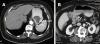

Intermittent gastric outlet obstruction due to a gallstone migrated through a cholecysto-gastric fistula: a new variant of "Bouveret's syndrome"

Bouveret's syndrome, defined as gastric outlet obstruction due to a large gallstone, is still one of the most dramatic biliary gallstone complications. Although new radiological and endoscopic techniques have made pre-surgical diagnosis possible in most cases and the death rate has dropped dramatically, "one-stage surgery" (biliary surgery carried out at the same time as the removal of the gut obstruction) should be still considered as the gold standard for the treatment of gallstone ileus.In this case, partial gastric outlet obstruction resulted in an atypical and insidious clinical presentation that allowed us to perform the conventional one-stage laparatomic procedure that completely solved the problem, thus avoiding any further complications.